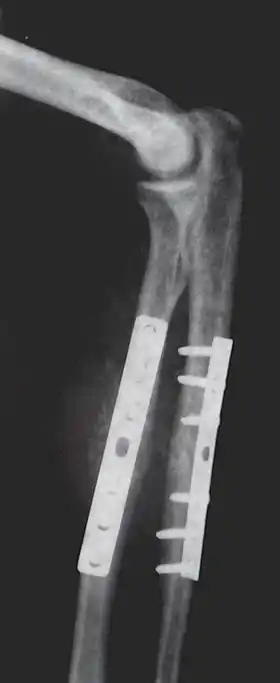

Orthopedic surgery or orthopedics (alternatively spelt orthopaedics) is the branch of surgery concerned with conditions involving the musculoskeletal system.[1] Orthopedic surgeons use both surgical and nonsurgical means to treat musculoskeletal trauma, spine diseases, sports injuries, degenerative diseases, infections, tumors, and congenital disorders.

The use of intramedullary rods to treat fractures of the femur and tibia was pioneered by Gerhard Küntscher of Germany. This made a noticeable difference to the speed of recovery of injured German soldiers during World War II and led to more widespread adoption of intramedullary fixation of fractures in the rest of the world. Traction was the standard method of treating thigh bone fractures until the late 1970s, though, when the Harborview Medical Center group in Seattle popularized intramedullary fixation without opening up the fracture.

External fixation of fractures was refined by American surgeons during the Vietnam War, but a major contribution was made by Gavril Abramovich Ilizarov in the USSR. He was sent, without much orthopedic training, to look after injured Russian soldiers in Siberia in the 1950s. With no equipment, he was confronted with crippling conditions of unhealed, infected, and misaligned fractures. With the help of the local bicycle shop, he devised ring external fixators tensioned like the spokes of a bicycle. With this equipment, he achieved healing, realignment, and lengthening to a degree unheard of elsewhere. His Ilizarov apparatus is still used today as one of the distraction osteogenesis methods.[12]

- Repair fracture of radius (bone)/ulna

- Repair of femoral shaft fracture